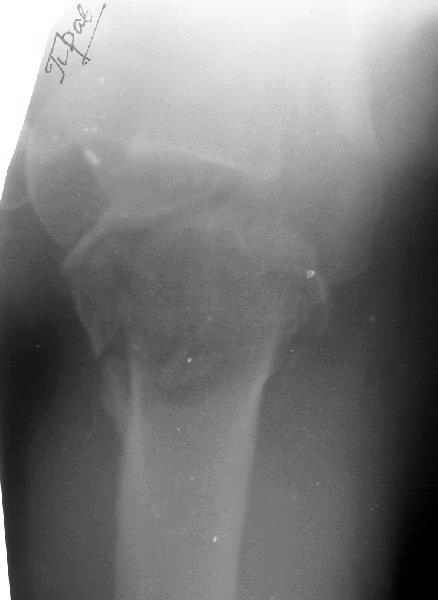

Мужчина 61 г., получил 6.04.02 в ДТП (лобовое столкновение) вывих плеча с переломом большого бугорка и не бросающимся в глаза переломоманатомической шейки (см здесь ). В ЦРБ под в/в наркозом дежурный врач (ЛОР по специальности) попытался вправить плечо. Контрольный снимок

сделан через день (фас, аксиальная). Из сопутствующей патологии - болезнь Рейно, 2 года назад какая-то сосудистая операция (выписки нет, 15 см рубец под мышкой), от которой положительного эффекта не отметил.Есть холодность и мраморность предплечья и кисти, стойкие контрактуры пальцев. Эндопротезирование плечевого сустава в число доступных методик не входит. Намереваемся сделать открытую репозицию и фиксировать пластинкой, если будет нестабильность, то и спицами трансартикулярно. Очевидно, что есть высокий риск аваскулярного некроза головки, о чем пациент предупрежден. Есть ли альтернативы такому плану? Может быть, какая-то подвешивающая операция тут предпочтительнее, или дополнить остеосинтез подвешиванием плеча к акромиону? Или вообще не оперировать, а пойти на раннюю функцию по стихании болевого синдрома? Заранее спасибо. -- Best regards, Alexander N. Chelnokov